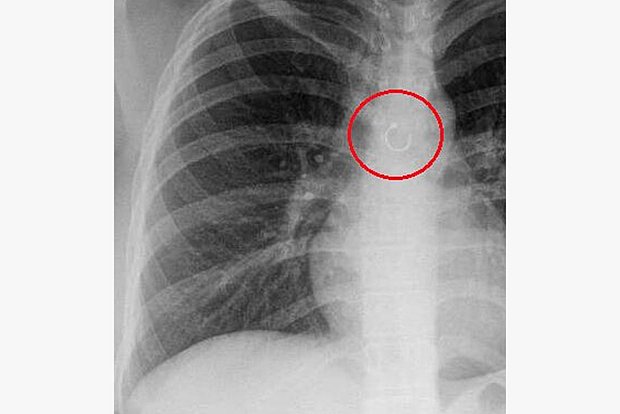

В легком у девушки нашли пирсинг носа

В Мексике из легкого девушки удалили пирсинг носа

Фото: @Whoisbarajas